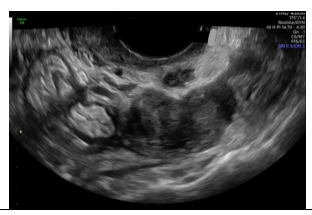

Paciente nulípara, sem uso de contraceptivos, comparece ao ginecologista com queixa de dispareunia e dismenorreia importantes, com piora cíclica no período menstrual. Apresenta a seguinte imagem ao exame de ultrassom endovaginal:

A imagem ecográfica sugere como diagnóstico

Paciente nulípara, sem uso de contraceptivos, comparece ao ginecologista com queixa de dispareunia e dismenorreia importantes, com piora cíclica no período menstrual. Apresenta a seguinte imagem ao exame de ultrassom endovaginal:

A imagem ecográfica sugere como diagnóstico